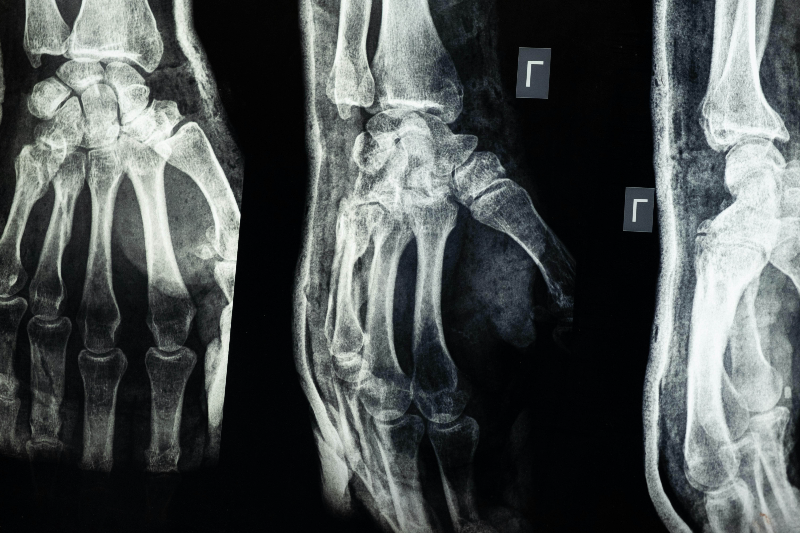

안녕하십니까, 관절염 종류에 하나인 류머티즘 관절염에 대한 이야기를 하려고 합니다. 류머티즘관절염은 손과 손목, 발과 발목 등을 비롯한 여러 관절에서 염증이 나타나는 만성 염증성 질환입니다. 오늘은 류머티즘 종류, 류머티즘 좋은 운동 10가지, 류머티즘 나쁜 운동 10가지에 대해 소개하겠습니다.